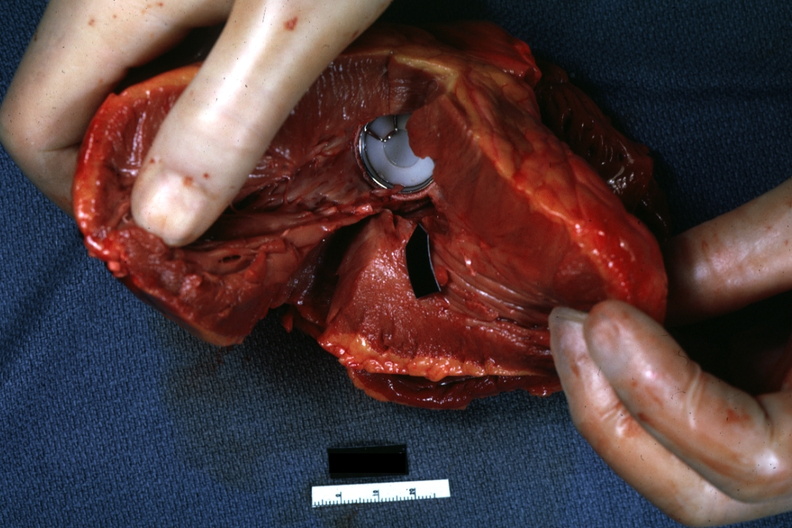

GROSS: CARDIOVASCULAR: HEART: Mitral Valve Prosthesis: Gross natural color view of left ventricle of Bjork Shiley disc type valve with white plastic disc an early model